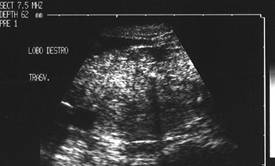

Femeie de 46 ani.Tumefactie voluminoasa a lobului stang, marcant hipoecogena, cu intarire posterioara, de 28x29x29mm (12 cc), cu echouri in interior si microcalcificari parietale.

Citoaspiratia: chist coloid.